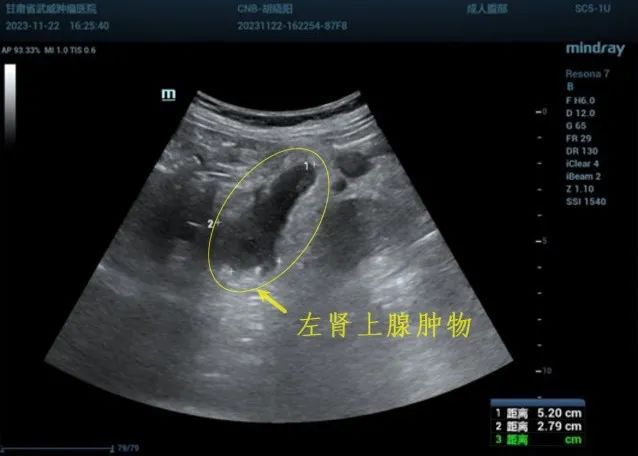

左侧肾上腺肿物穿刺活检

左肾上腺肿物 超声引导下穿刺活检